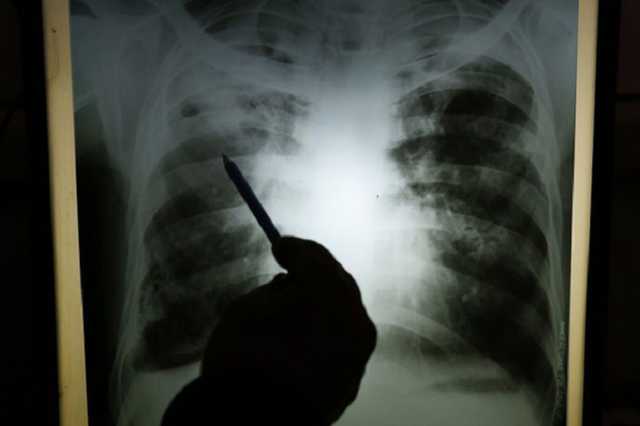

На Буковині 9-річний хлопчик помер від пневмонії

На Буковині батько дитини звинувачує медичних працівників у неправильному діагностуванні хвороби та неналежному виконанні професійних обов’язків, що призвело до смерті його сина.

Чоловік повідомив, що в ніч на 15 березня у його 9-річного сина погіршилося самопочуття. Батьки викликали карету швидкої медичної допомоги, яка доставила малолітнього до лікарні.

Пізніше, цього ж дня, хлопчик помер у реанімаційному відділенні. За вказаним фактом слідчі Чернівецького районного управління поліції внесли відомості до Єдиного реєстру досудових розслідувань за частиною 2 статті 140 (Неналежне виконання професійних обов’язків медичним або фармацевтичним працівником) Кримінального кодексу України.